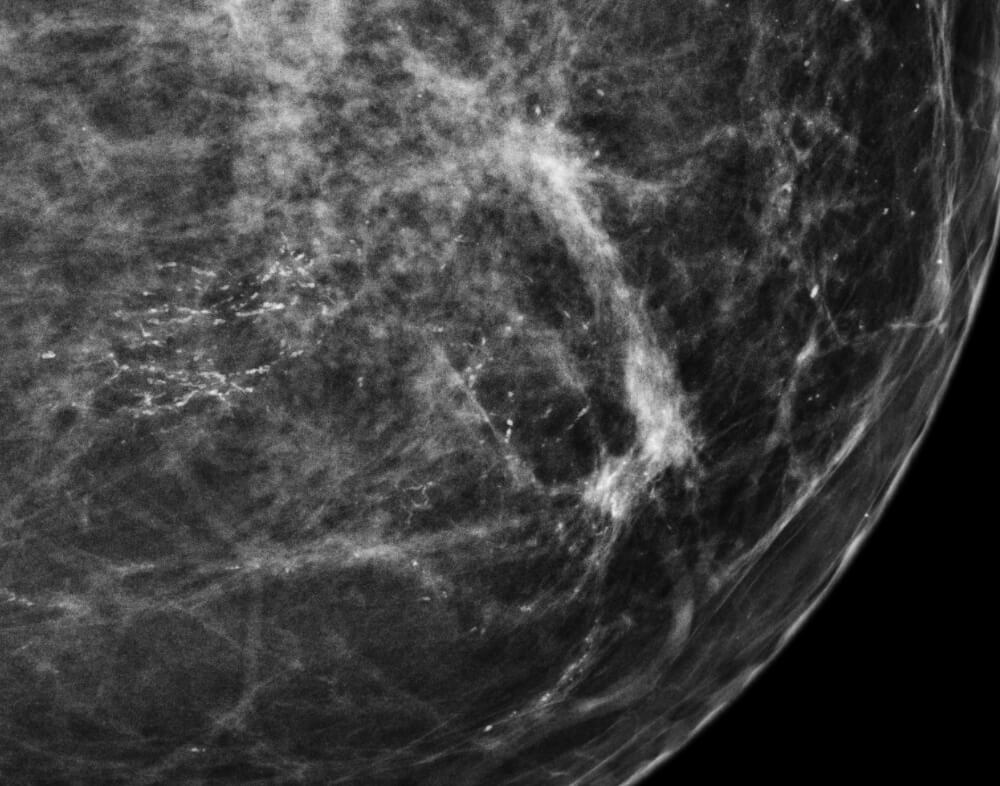

Οι επασβεστώσεις του μαστού είναι εναποθέσεις ασβεστίου μέσα στον ιστό του μαστού. Είναι εμφανείς στην μαστογραφία σαν λευκά σημάδια ποικίλου σχήματος και μεγέθους.

Ανάλογα με το μέγεθός τους διακρίνονται σε μακροεπασβεστώσεις και μικροεπασβεστώσεις.

Οι μακροεπασβεστώσεις είναι μεγάλες αδρές εναποθέσεις ασβεστίου που σχεδόν ποτέ δεν σχετίζονται με την ανάπτυξη κακοήθειας και δεν χρειάζονται επιπλέον έλεγχο και αντιμετώπιση.

Οι μικροεπασβεστώσεις είναι μικροσκοπικές εστίες ασβεστίου και σε μερικές περιπτώσεις μπορεί να σχετίζονται με την ανάπτυξη κακοήθειας, γι' αυτό και απαιτούν επιπλέον διερεύνηση.

Οι μικροεπασβεστώσεις χαρακτηρίζονται ως αθώες ή ύποπτες ανάλογα με ορισμένα χαρακτηριστικά τους, όπως η μορφή, το μέγεθος, η πυκνότητα και η κατανομή τους.